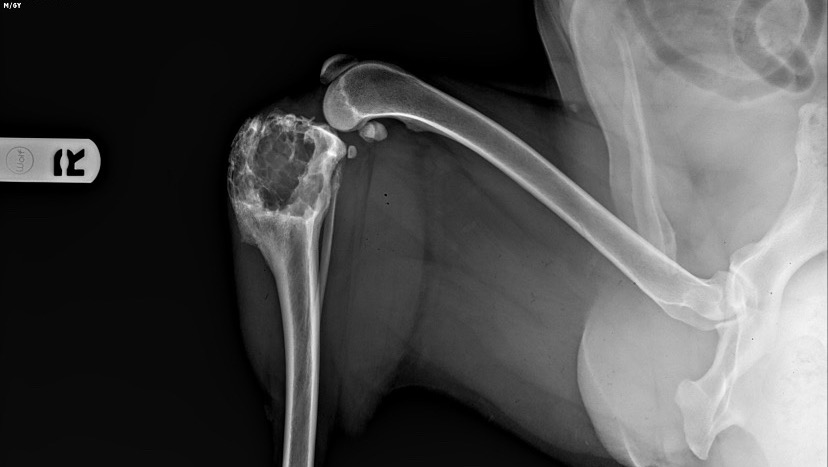

Hi my name is Clyde and my family needs help . We have been told my leg needs to be amputated before the problem gets worse and my bone breaks causing me extreme pain and agony . My human has taken me to many different vets and some even suggested I be put down if we can’t afford the treatment . Currently , I need a chest X-ray and a stomach ultrasound before attempting to remove my leg , but we don’t have much time . My human is trying to do everything she can , I even told her she can take me to a rescue , but no rescue will help us . We have tried everything and I can slowly see her losing hope , it’s very sad to my mom because she sees an enormous will to live in me and she knows I would make a great 3legged friend . Someone suggested GOFUNDME today, so we will give this a try . Maybe a veterinarian or a rescue will come across this and be able to help us . If you are not able to donate today , we ask that you please say a prayer for me . So that we can find the help we need before it’s too late. Thank you to everyone who took the time to read about me , god bless you all